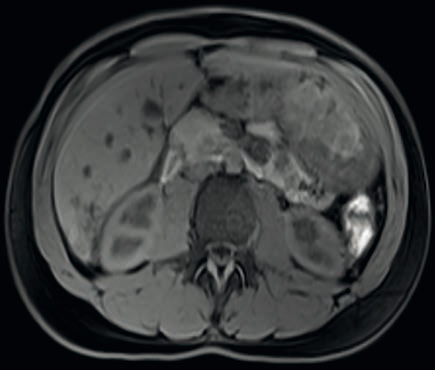

Figure 6 : Coupe axiale T1 avec saturation de la graisse

Description de l'IRM hépatique

• Multiples petits kystes confluents en hypersignal T2, hyposignal T1, de paroi fine se rehaussant après injection de produit de contraste.

• De siège intra-hépatique (segment VI), sur foie sain.